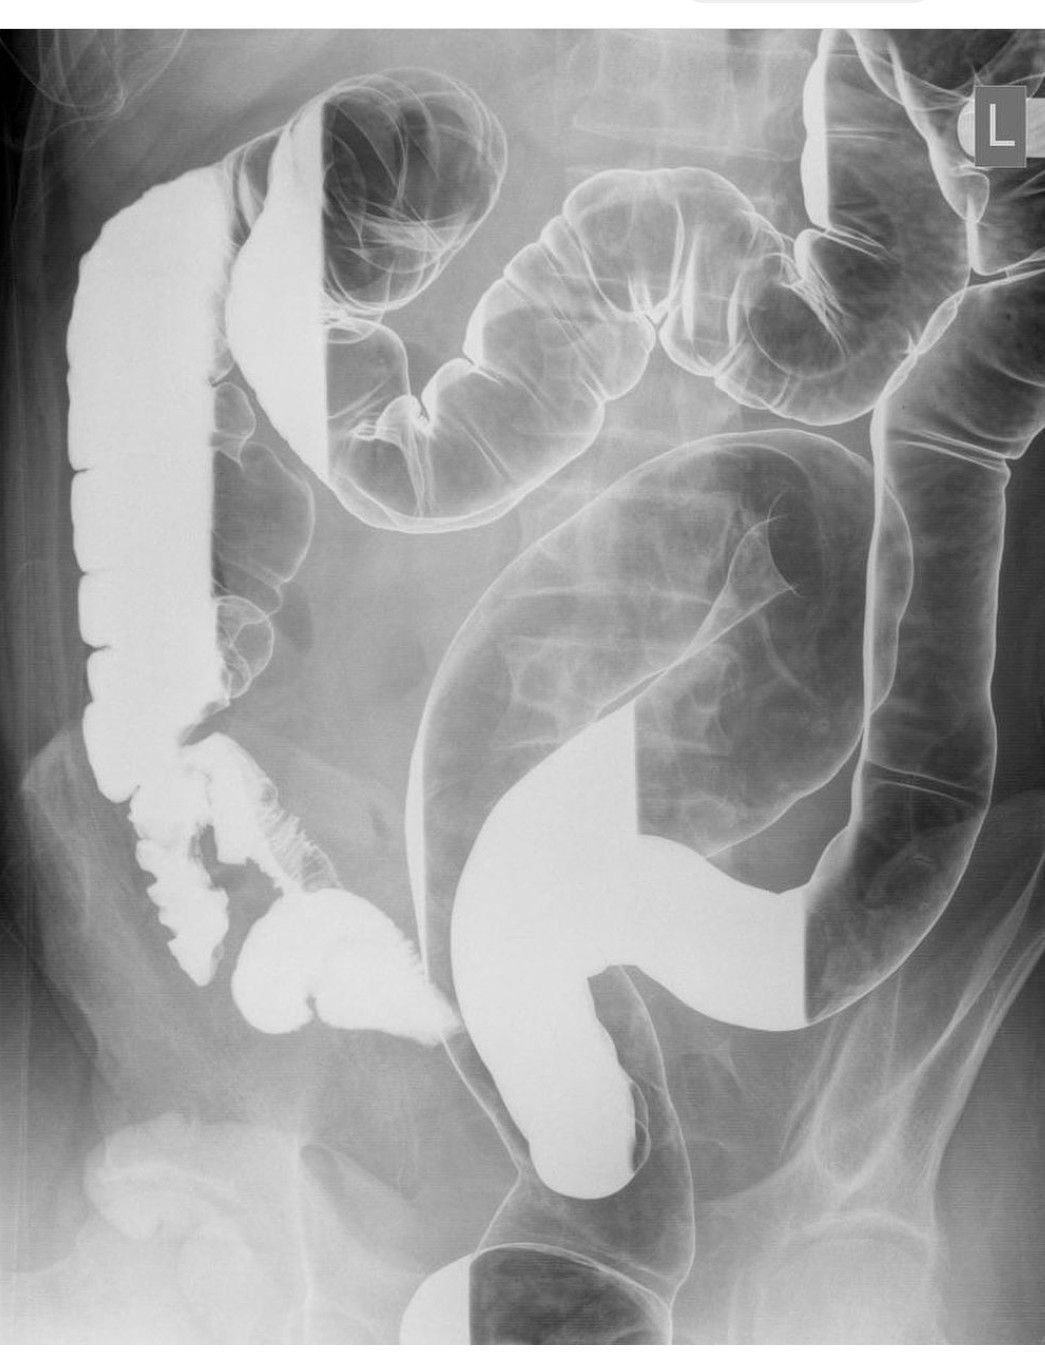

Lead Pipe Appearance

Lead pipe appearance of colon in ulcerative colitis.